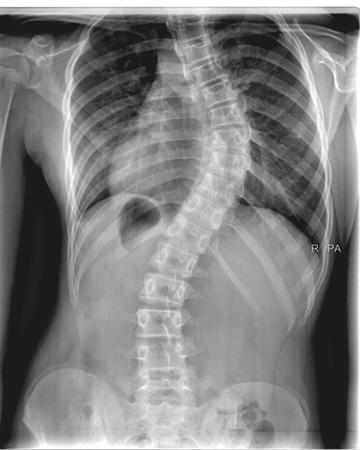

The human spine has a natural forward and backward curve. Scoliosis is an abnormality in the spine wherein it curves sideways. It affects about 2% of people in the world. The curve could be either to the left or right, and it forms a C or S shape. Any curve more than 10 degree is diagnosed as scoliosis. People with scoliosis suffer from back pain, leg pain, and weakness. Their core muscles weaken and they find it difficult to stand upright.

In advanced cases of scoliosis, a curve on the back is clearly visible. Uneven shoulders and displaced hips are also quite apparent.

- Imaging tests such as MRIs or X-rays are used to quantify the angle and severity of the curve after a physical examination to identify spinal asymmetry. Mild instances may require routine monitoring.